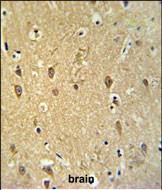

IHC 1/100-1/500 Human,Mouse,Rat

GPR17 is a class A G protein-coupled receptor (GPCR) implicated in myelination, neuroinflammation, and tissue repair. Initially orphan, it was later found to respond to purinergic (e.g., UDP-glucose) and cysteinyl-leukotriene ligands, linking it to dual signaling pathways. GPR17 is highly expressed in oligodendrocytes, astrocytes, and specific neuronal populations, with roles in CNS development, injury response, and diseases like multiple sclerosis, stroke, and neurodegenerative disorders.

GPR17 antibodies are critical tools for studying its expression, localization, and function. They enable detection via techniques such as Western blotting, immunohistochemistry, and flow cytometry. Most antibodies target extracellular domains (e.g., N-terminus) or intracellular loops, with species-specific variants available for human, mouse, and rat models. Commercial antibodies are widely offered by suppliers like Abcam, Sigma-Aldrich, and Santa Cruz Biotechnology.